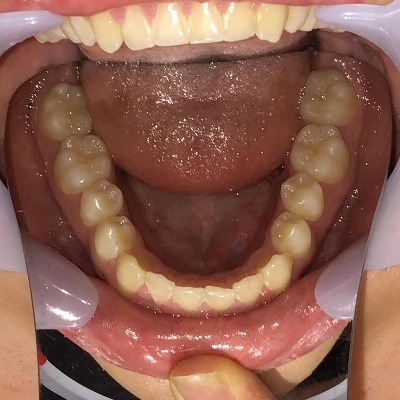

下顎

| 治療内容 | インビザライン 全顎 |

| 治療詳細 | 反対咬合や叢生を整えるために、歯の表面にアタッチメント(白い突起)をつけ、IPR(歯と歯の間を削る)を行いました。 また、顎間ゴムと呼ばれる上顎と下顎に渡って引っ掛けるゴムの補助装置も用いて治療を行いました。 |

| 患者情報 | 10代 男性 デンタルモニタリング使用 |

| 主訴 | 下顎が前に出ている(受け口) 歯のがたつき |